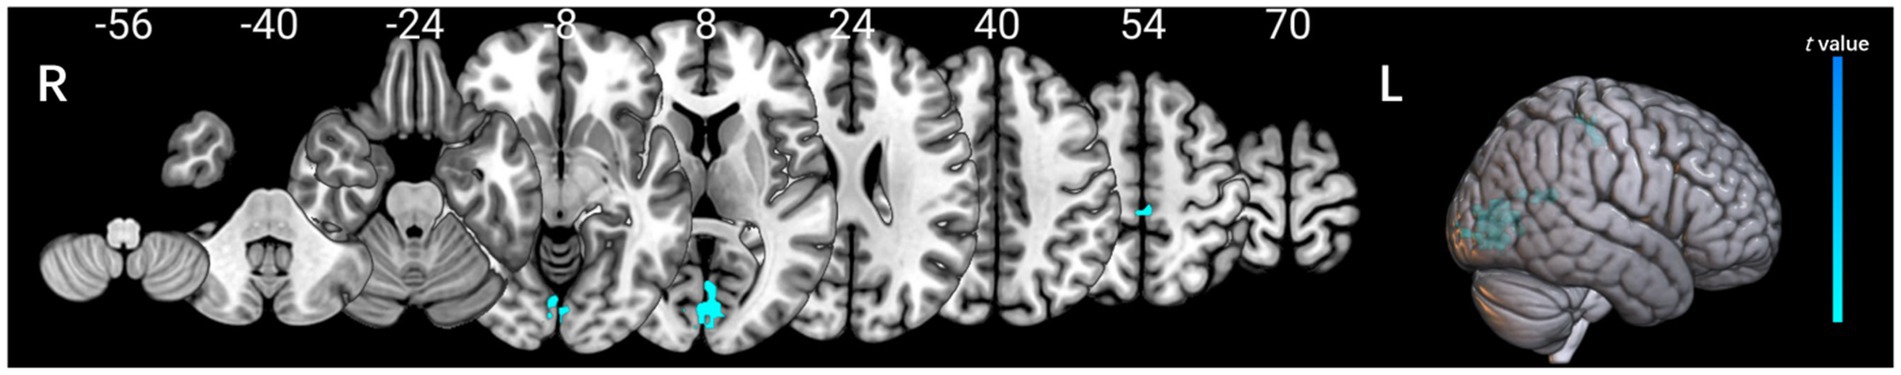

Volume-wise and voxel-wise Rs-fMRI concordance alterations in patients with POAG

Patients with POAG exhibited a significantly decreased mean value of volume-wise Rs-fMRI concordance compared to HCs (p < 0.001) (Figure 3). Significant differences in voxel-wise Rs-fMRI concordance between patients with POAG and HCs are shown in Figure 4. We found decreased voxel-wise Rs-fMRI concordance in multiple regions, including bilateral lingual gyrus (LING.L/R), calcarine fissure and surrounding cortex, and left posterior cingulate gyrus (p < 0.001).

Figure 4

Comparison of the voxel-wise Rs-fMRI concordance between patients with POAG and HCs.

The cool color regions representing significantly reduced Rs-fMRI concordance in patients with POAG (GRF, voxels p < 0.001, clusters p < 0.05). POAG, Primary open angle Glaucoma; HCs, healthy controls.